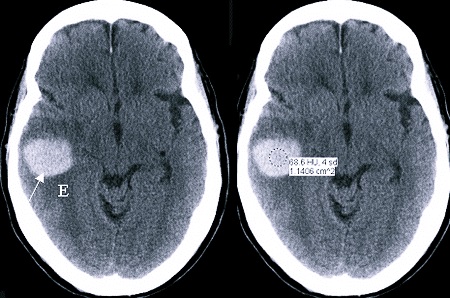

Новообразования

Образование интракраниальной опухоли – спонтанного и неконтролируемого деления клеток в черепе – сопровождается тяжестью в голове. Между мозгом и черепной коробкой немного пространства, а патологически разрастающаяся ткань в черепе начинает давить на головной мозг, так как место для ее расширения отсутствует. Это давление и вызывает сильную боль с чувством, того, что голова становится тяжелой.